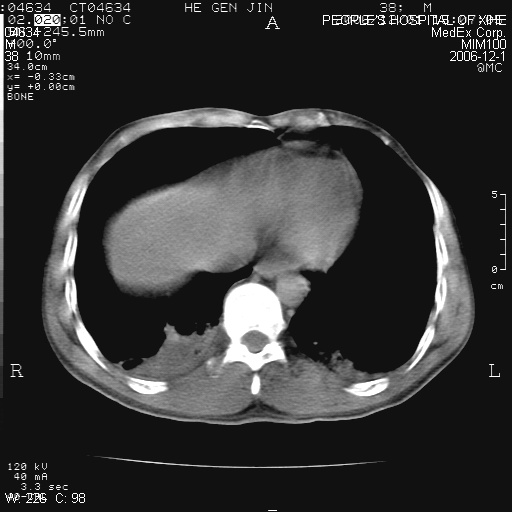

此片根本无法看,一幅纵隔窗而没有这幅图像的肺窗.不好发表意见.

什么资料都没有,照片质量也不好,还没有纵隔窗,怎么讨论?